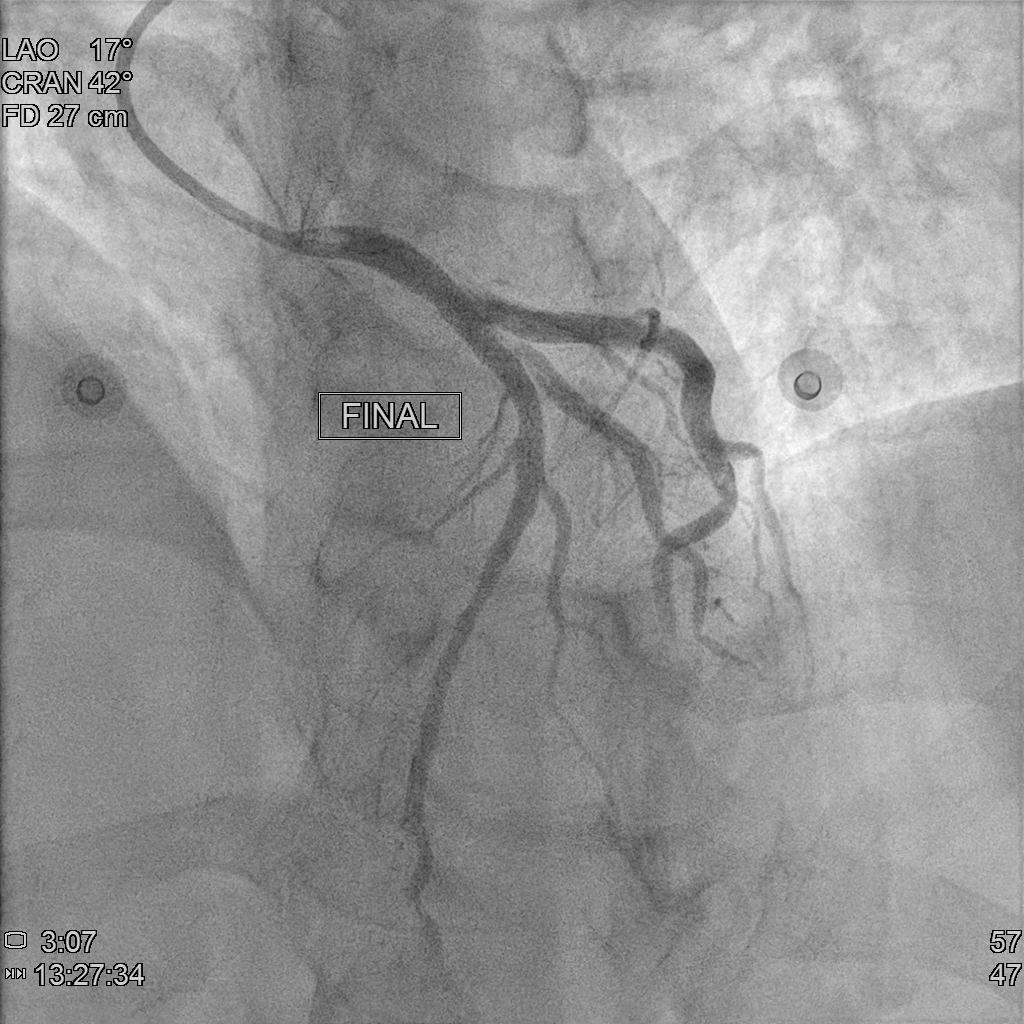

Coronary angiography showed CAD(1-V-D), with medina 1.1.1 bifurcation lesion at LAD-P and LAD-D1. We decided to performed provisional stenting strategy. We accidentally retracted the jailed wire after MV pre-dilation and TIMI flow of SB decreased to TIMI 1. It was difficult to rewire to SB due to acute take off angle after MV pre-dilation, so we performed DLC facilitated RWT. After that, we performed DK crush technique for the bifurcation lesion. The final angiography looks good.

Under support of Boston JL3.5,6Fr via Left Radial Artery approach, we introduced Floopy wire to LAD-D and Pilot 50 wire to LAD-D1. We dilated the 99% stenosis of LAD-M and LAD-P with Trek 2.5x20mm to 10 ATM. We checked the the intracoronary artery condition with IVUS and revealed severe stenosis and massive plaque burden in LAD-P to M and the lesion lenght of LAD-D1 orifice was 4.31mm with severe stenosis. After image evaluation, we used NC Trek 3.5x20mm to 12 ATM for predilatation, however, we incidentally retracted the LAD-D1 wire and we found that the flow of LAD-D1 became worse due to carina and plaque shift. It is challenging for direct wire and thus we perfomred reverse wiring technique with double lumen catheter (Crusade R). After that, we perfomred two stent strategy with DK crushing technique. We predilated the LAD-D1 with Trek 3.0 x15mm to 12 ATM. Then we deployed (NEW)SYNERGY XD 3.0 x20mm to LAD-D1, and crushed it with NC Trek 3.5x20mm to 12 ATM. Then we used CONQUEROR康克爾 4.0 x20mm to 20 ATM for POT followed by first kissing ballon technique with NC Trek 3.5x20mm to LAD and Trek3.0 x15mm to LAD-D1 to 8 ATM. After that, we deployed (NEW)SYNERGY XD 3.5x48mm to 12 ATM at LM to LAD-M. We performed POT with NC Trek 4.5x 8mm to 12 ATM followed by second KBT with the same balloones used during first KBT. We check the IVUS and performed the final POT with Trek 5.0 x12mm to 20 ATM due to malapposition noted at proximal site of stent. The final angiography looks good.